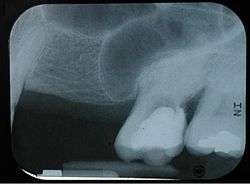

The maxillary sinus can normally be seen above the level of the premolar and molar teeth in the upper jaw. This dental x-ray film shows how, in the absence of the second premolar and first molar, the sinus became pneumatized and expanded towards the crest of the alveolar process (location at which the bone meets the gum tissue).